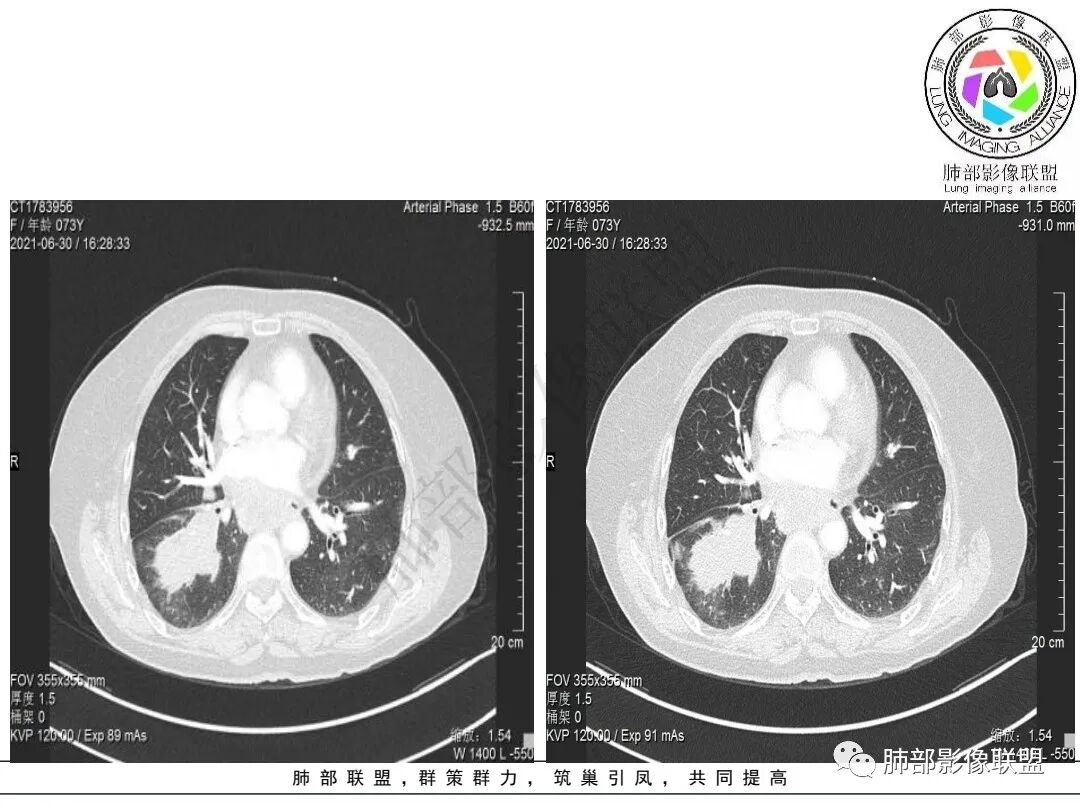

2.右肺下叶不规则实性密度块影,占据外后基底段及背段较大范围,可见轻度分叶、毛刺及棘状突起,未见明显胸膜牵拉及凹陷。

3.右肺下叶支气管轻度狭窄,病灶内见部分充气支气管征,外后基底段不能连续跟踪。

轻度不均匀强化,病灶内小血管显示不满意,未见明确坏死区。

4.右肺门及纵隔见多处增大淋巴结,不均匀环形强化,后下纵隔(隆突下)肿大淋巴结十分显眼!